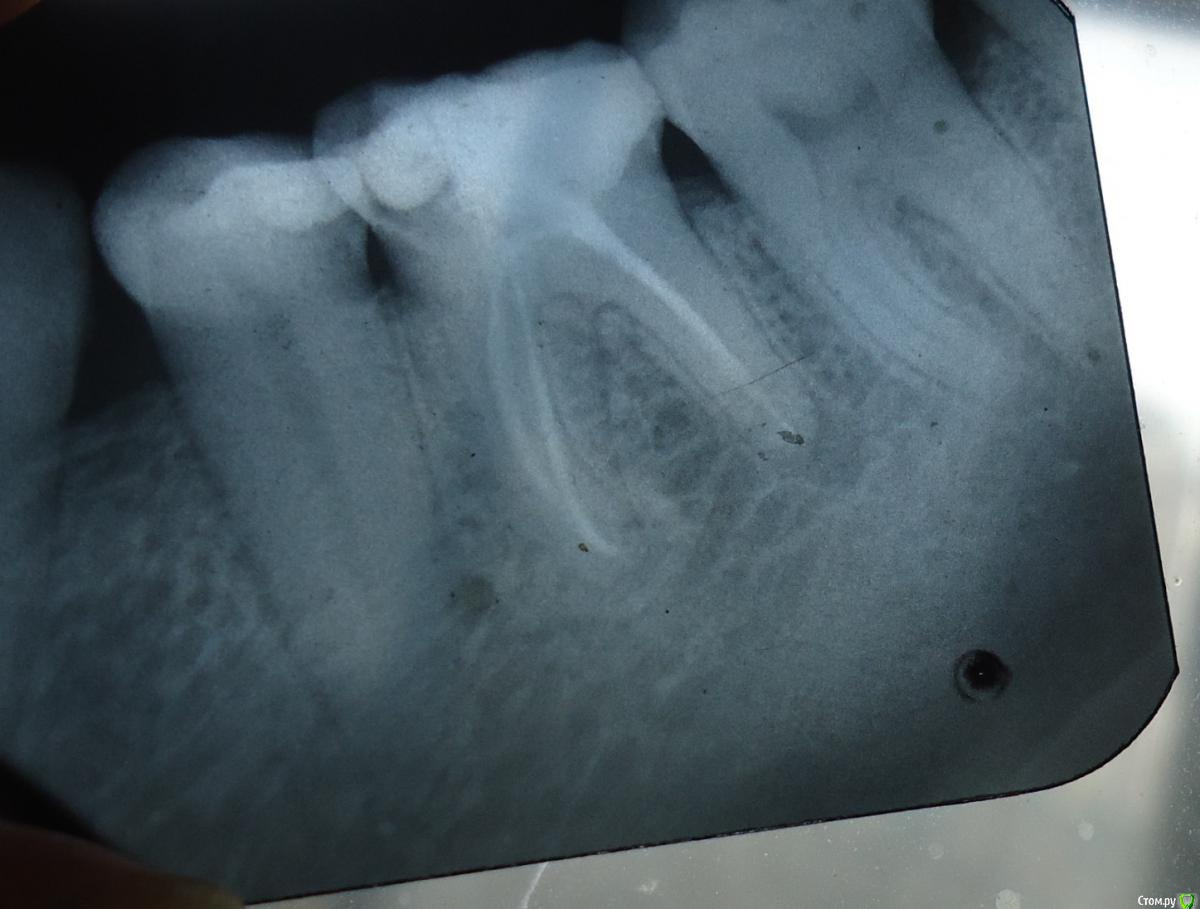

натg Опубликовано 2 апреля, 2015 Поделиться Опубликовано 2 апреля, 2015 (изменено) Здравствуйте, веду спор с врачем. Уменя большая дырка в по-моему 6 зубе внизу, врач ставит на эту дырку 2 пломбы из 2 кусков, они , эти куски, находятся рядом. Получается так, что одна часть этой пломбы, которая прилепливается к другой части пломбы, поставленной отдельно в другое время, все время отпадает, тогда врач ее долепливает. Я требовала заменить пломбу из 2 кусков цельной, чтобы не было отпадения куска, но врач говорит- это хороший материал, дырка большая, показана коронка, скажите спасибо, что я соглашаюсь ставить пломбу. Вот уже второй год хожу с этим зубом, и эта часть, которую долепливают, отпадает раз в пол-года, ее прилепливают опять. Сейчас она опять отпала. Вопрос- целесообразны ли действия врача, который вместо того, чтобы поставить цельную, долепливает? Пломба большая на жевательной поверхности, отпадает точно по месту прилепливания. На пломбу большое давление, я не понимаю, почему не ставит цельную? Смысла в коронке не вижу, так как я так понимаю, это никогда не поздно сделать. Канал запломбирован в этом зубе, или их там два, точно не помню, это второй квадратноватый, если смотреть спереди, внизу. Объясните пожалуйста, в чем смысл коронки, ведь для этого надо обточить весь зуб, а это можно всегда успеть сделать? Помоему, 2 пломбы рядом прилепленые только снижают прочность конструкции. На фото старый снимок, около 1.5 лет. Почему не хочу делать коронку- на фото возле конца одного канала внизу странное пятно, советовали ждать, что там будет, говорили, что там что-то непонятное, подозрительное. Что касается ситуации с разрушением зуба сейчас- передняя его стенка, та, что ближе к передним зубам, сломалась. Почему не хочу коронку- дорого и непонятно, чем закончится то, что на конце канала, потом туда лезть снимать коронку и все переделывать будет сложно. В раздумиях хожу уже неделю с дыркой на ползуба, остальная половина зуба с пломбой, если ли вероятность распломбировки каналов, пока хожу ищу консультанта? Изменено 2 апреля, 2015 пользователем натg Ссылка на комментарий

Гарриевич Опубликовано 2 апреля, 2015 Поделиться Опубликовано 2 апреля, 2015 по снимку зуб нужно покрывать коронкойв противном случае рискуете вообще его потерять 2 Ссылка на комментарий

red_butler Опубликовано 2 апреля, 2015 Поделиться Опубликовано 2 апреля, 2015 Прикрепили снимок, теперь все встало на свои места. Требуется повторное лечение корневых каналов с последующим протезированием корневой вкладкой и коронкой.Слушайте своего врача Ссылка на комментарий

red_butler Опубликовано 2 апреля, 2015 Поделиться Опубликовано 2 апреля, 2015 каналы ровные на снимке, я так вижу, мне никто их перелечивать не предлагал, если они до сих пор ровные какой смысл перелечивать7в области верхушки одного из корней воспалительный очаг, это может быть следствием инфекции в корневом канале, если хотите сохранить зуб - перелечивайте Ссылка на комментарий

Zlata-doctor Опубликовано 11 мая, 2015 Поделиться Опубликовано 11 мая, 2015 1. Повторное эндолечение шестого зуба ( там есть очаг воспаления-это очевидно). Ищите хорошего эндодонтиста, если хотите иметь этот зуб. 2. Протезирование шестого зуба3. На первом снимке довольно большая полость 5 зуба ( живого), пораженная поверхность контактирует с 6 зубом, на втором снимке этой полости не видно, возможно потому, что снимок сделан с другого ракурса--еще раз сделать качественный снимок и подтвердить или опровергнуть мое предположение.4. Что вас заставляет спорить, как вы пишите, с врачом и упорно ходить "долепливать" одну и ту-же проблему? Ссылка на комментарий